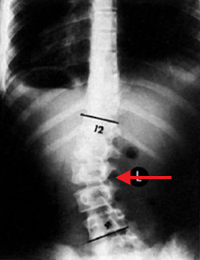

يتم التشخيص بالفحص السريري و الأشعة , و سوف نذكر طريقة قياس زاوية الإنحناء من الأشعة و التي تُسمى طريقة كوب Cobb Method و كذلك يُطلق على الزاوية زاوية كوب Cobb Angle . و تُقاس من صورة الأشعة السينية بالطريقة التالية:

" تعيين الفقرات التي تحدد الطرف العلوي و الطرف السفلي للإنحناء. و هذه الفقرات هي أشد فقرات الإنحناء ميلاناً تجاه الجهة المُقعرة للإنحناء.

" بعد تعيين الفقرتين , يُرسم خط مستقيم يمر بالطرف العلوي للفقرة العلوية للإنحناء و خط مستقيم آخر يمر بالطرف السفلي للفقرة السفلية للإنحناء.

" تُحسب الزاوية التي تقع عند تقاطع هذين الخطين و هي زاوية الإنحناء.

و كذلك بالأشعة يمكن معرفة ما إذا كان الجنف (الإنحناء) بنيوي أو مُعاوض (تعويضي) Compensatory Curvature , الإنحناء المُعاوض يحدث نتيجة للإنحناء البنيوي ليتوازن الجسم. تُأخذ صورة أشعة للشخص و هو منحني جانبياً لليمين و أخرى و هو منحني جانبياً لليسار, مما يؤدي إلى إختفاء الإنحناء المُعاوض و لكن الإنحناء البنيوي يظل. و هذه الطريقة كذلك تفيد في معرفة مرونة العمود الفقري لدى المريض.

في الصورة, في حال الوقوف الجنف يكون صدري قطني أيسر, عند الإنحناء يساراً لا يختفي الإنحناء الصدري لأنه بنيوي , و لكن عند الإنحناء يميناً يختفي الإنحناء القطني مما يعني بأنه مُعاوض و ليس بنيوي.

الفقرات باللون الأحمر = الفقرات الصدرية و الفقرات باللون الأصفر= الفقرات القطنية.